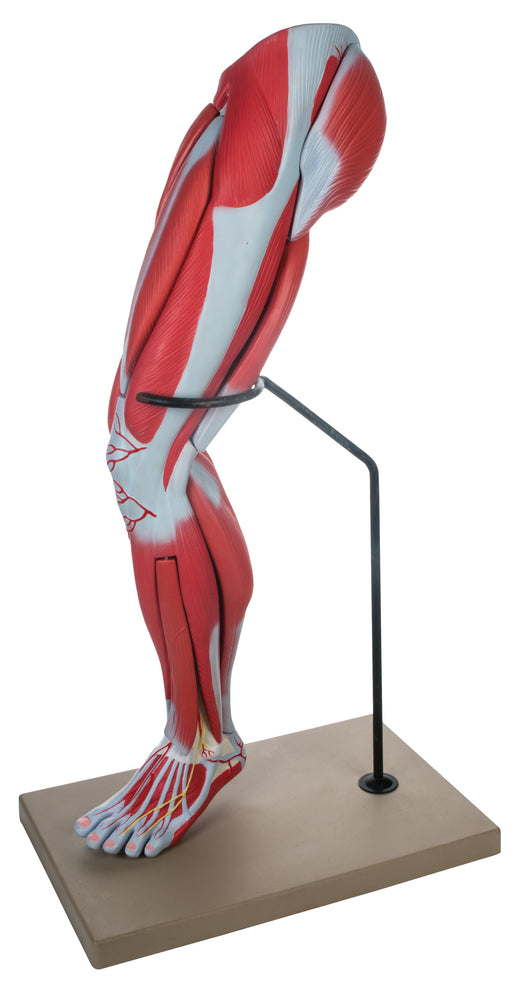

Muscular Leg - 9 Parts

The muscular leg model illustrates both the superficial and deeper muscles, eight of which are removable. Tendons, vessels, nerves and bone compone...

View full detailsAM16032 -